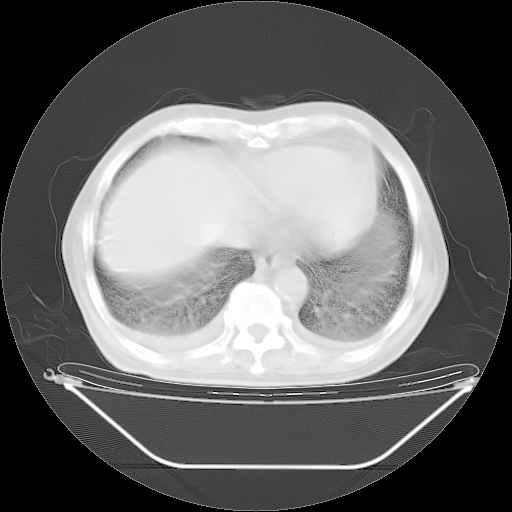

今天复查肺部CT,发现双肺广泛磨玻璃样改变。所以我把3月19日和5月9日相隔50天的肺部CT上传。请大家会诊。

2009年3月19日肺部CT片。

2009年3月19日肺部CT

大致读了系列胸部CT:纵隔窗无明显异常,肺窗:从4、27至今:主要是双肺中下野外带可见毛玻璃样改变,目前处于急性肺泡炎阶段,至于原因考虑1、结替组织或胶原血管性疾病所致?2、恶性疾病如恶组在肺部所致的表现或细支气管肺泡癌?3、药物或其它原因如肺蛋白沉着症所致肺泡炎目前不太可能?总之,明天就去请我院的呼吸科、感染科、血液科和临免专家会诊哈。